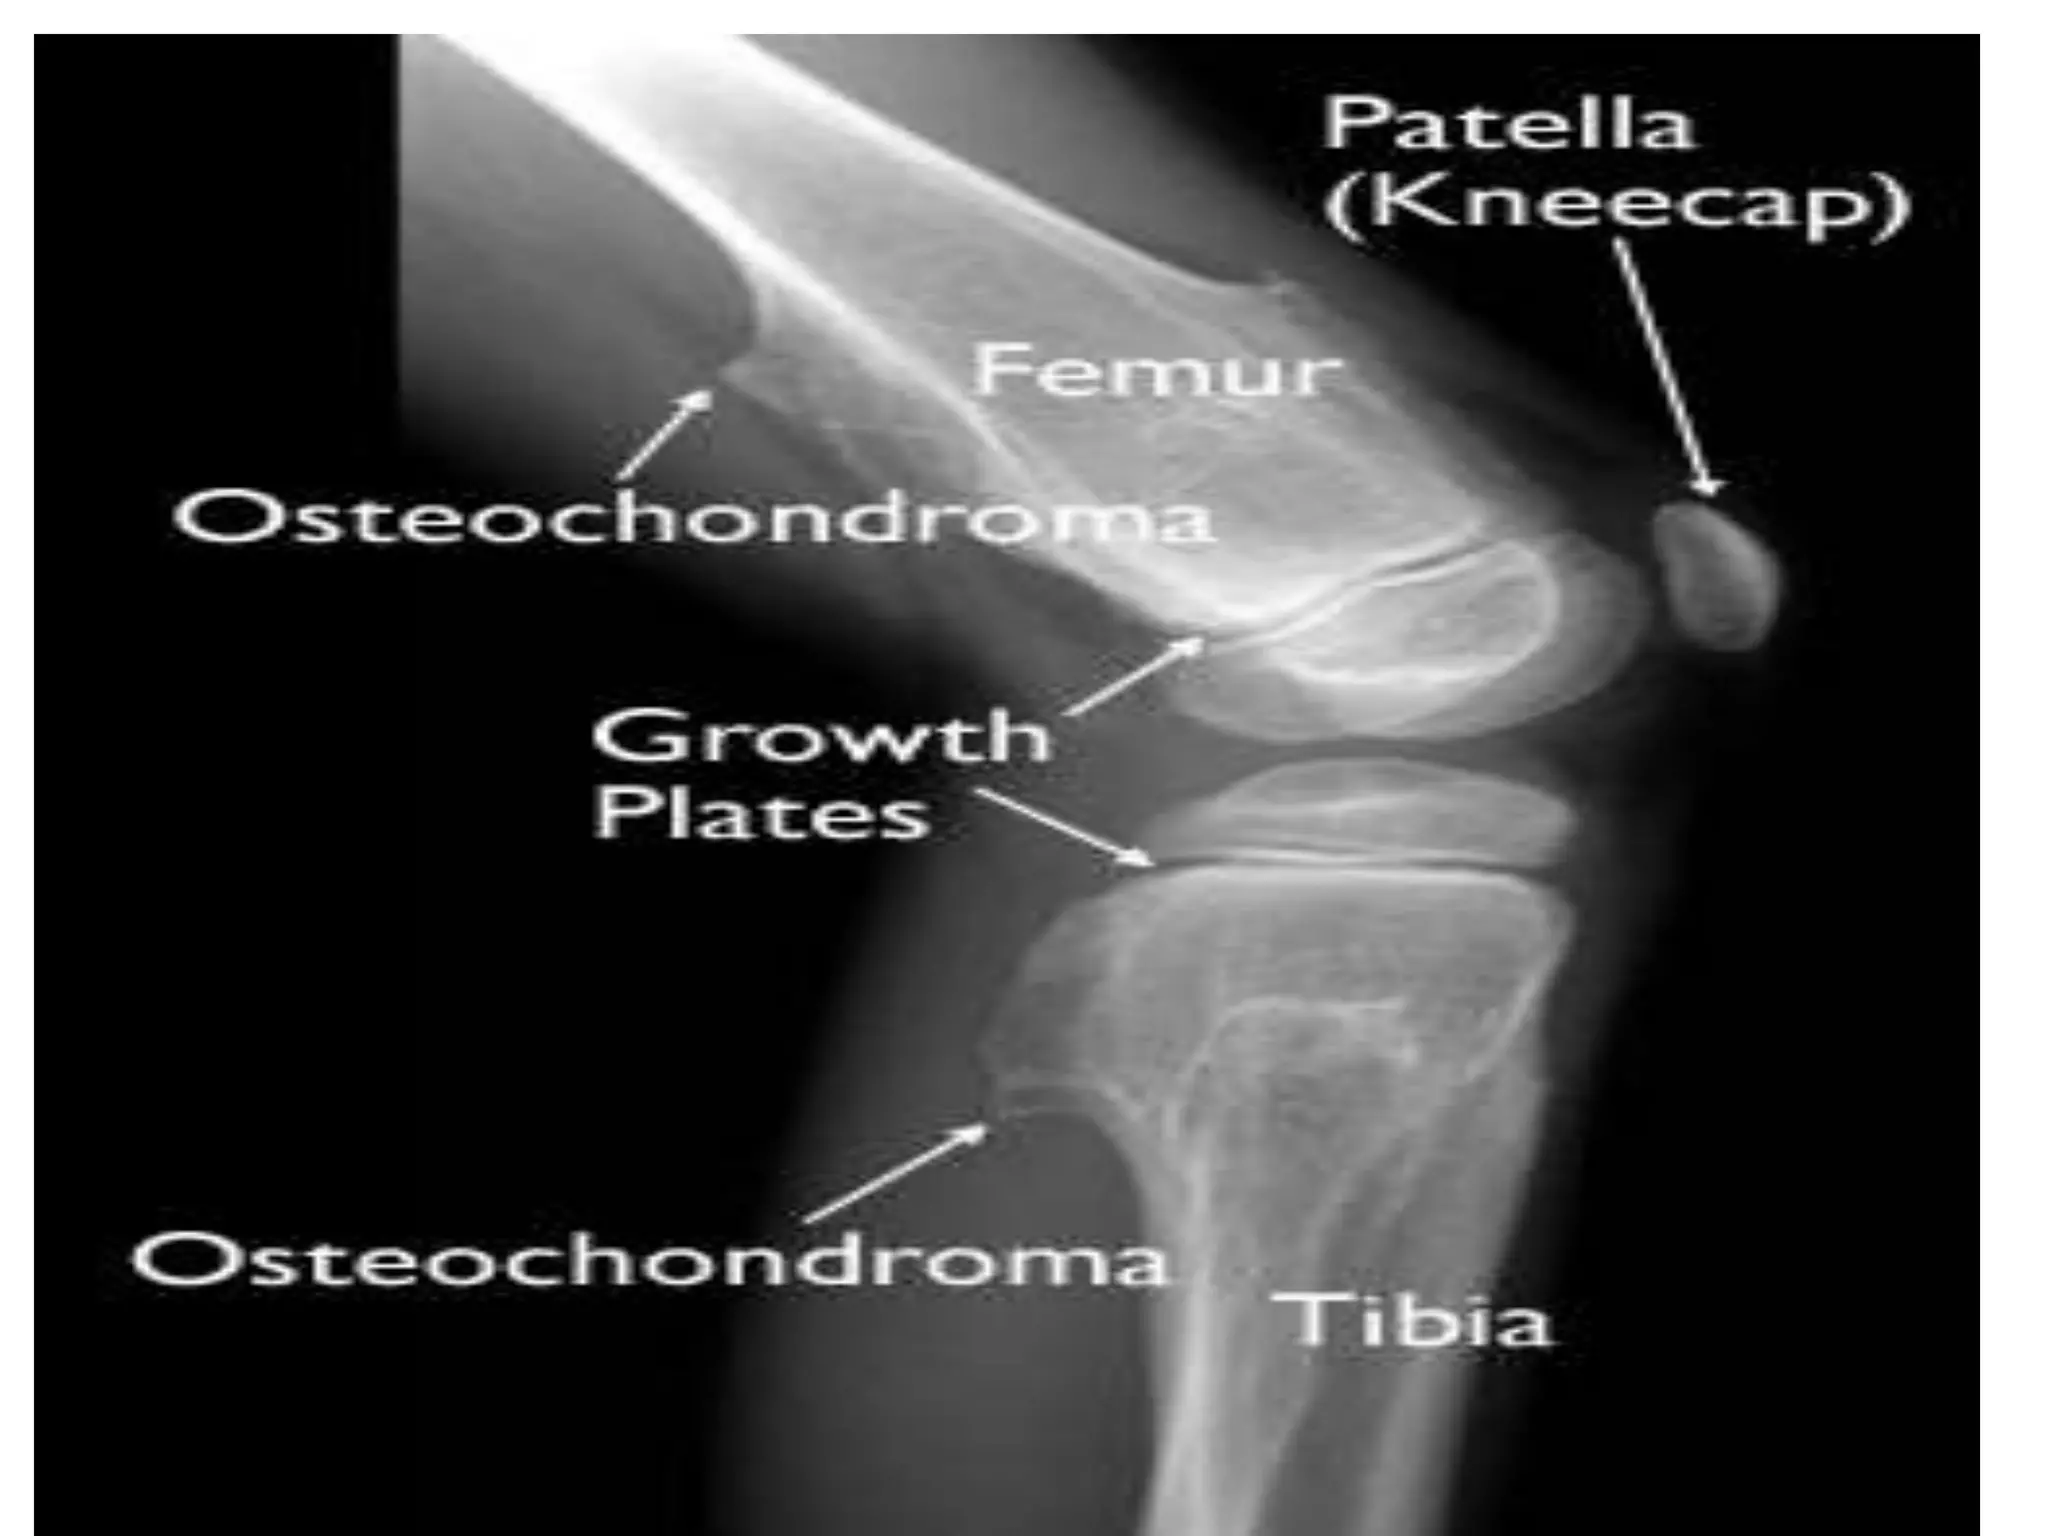

X ray findings, investigations

• X ray

– Bony growth made up of mature cortical bone

• Most common benign skeletal tumor, affects

persons 10-35 years of age

• outgrowth of the growth plate (made up of both

bone and cartilage)

• Increase in size

• Stops growing in adults

• can develop as a single tumor

(osteocartilaginous exostosis) or as many tumors

(multiple osteochondromatosis)